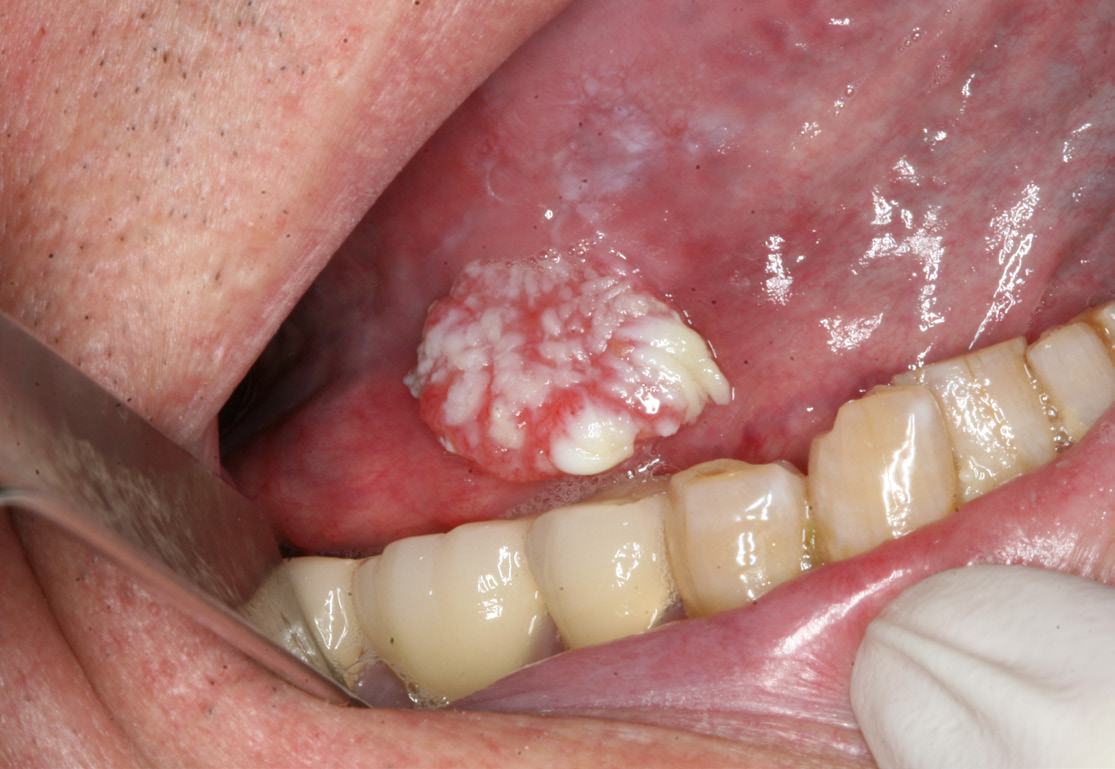

Oral Pathology 2 / 2023 - 2024